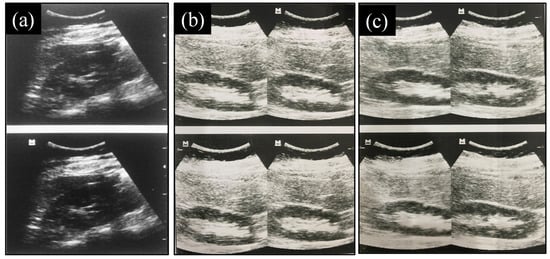

2.9.3. Evaluation of Images Produced

3.9.3. Evaluation of Images Produced